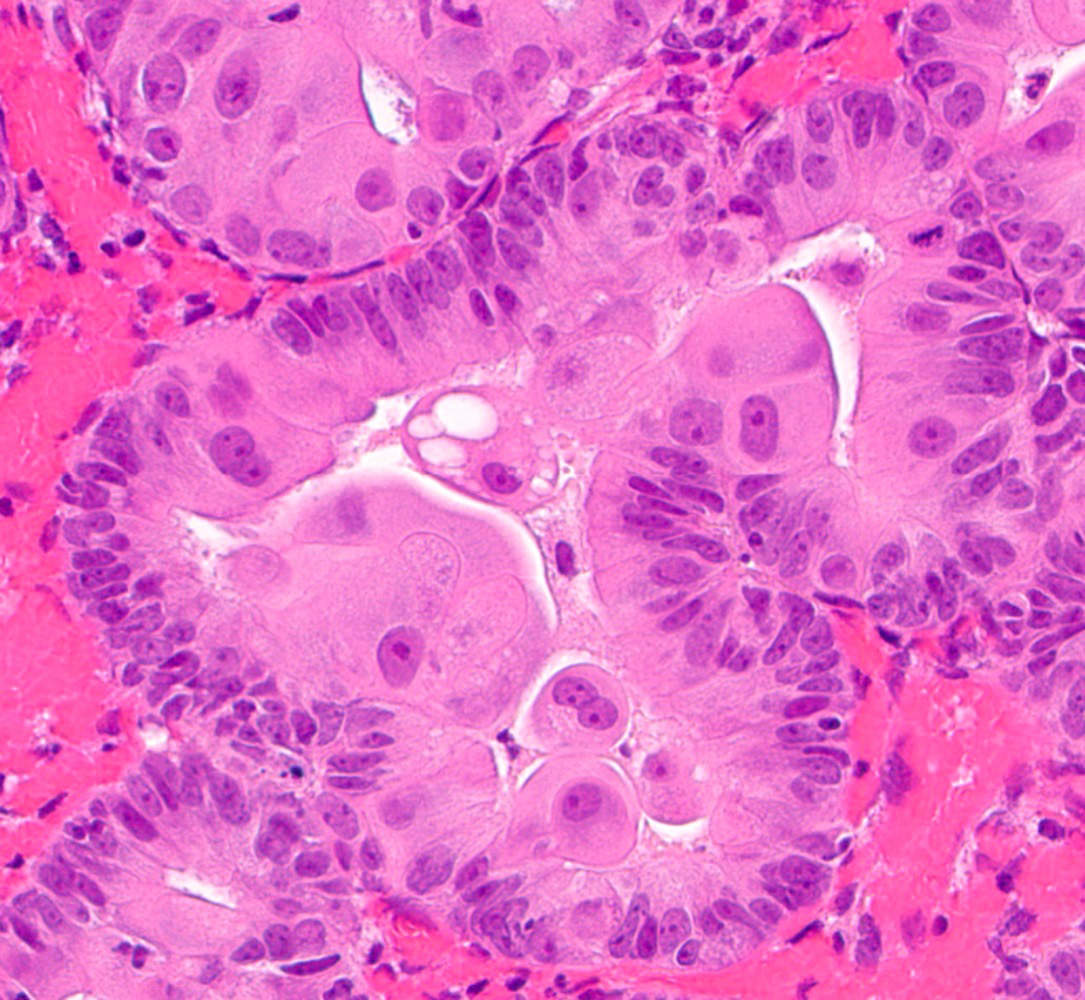

Microscopic (histologic) images

Contributed by Jessica L. Bentz, M.D.

- Tubal metaplasia (Mod Pathol 2011;24:1254):

- Resembling fallopian tube epithelium; pseudostratified with ciliated eosinophilic cells and clear round cells

- Papillary metaplasia (Am J Surg Pathol 2013;37:167):

- Papillary syncytial: pseudostratified eosinophilic cells with indistinct cell borders and loss of nuclear polarity (Int J Gynecol Pathol 2012;31:206)

- Sometimes termed as pseudopapillary due to the absence of fibrovascular cores

- Generally located on the surface

- Associated with stromal breakdown

- Papillary proliferations: true papillae with fibrovascular cores (Am J Surg Pathol 2001;25:1347)

- Simple / localized: short, nonbranching

- Complex / diffuse: numerous branching with papillae and micropapillae

- Analogous to endometrial intraepithelial neoplasia / atypical hyperplasia

- Hobnail metaplasia:

- Glandular, often eosinophilic cells with apically located nuclei that protrude into the lumen

- Can have cytoplasmic vacuolization

- Generally cytologically bland

- Glandular, often eosinophilic cells with apically located nuclei that protrude into the lumen